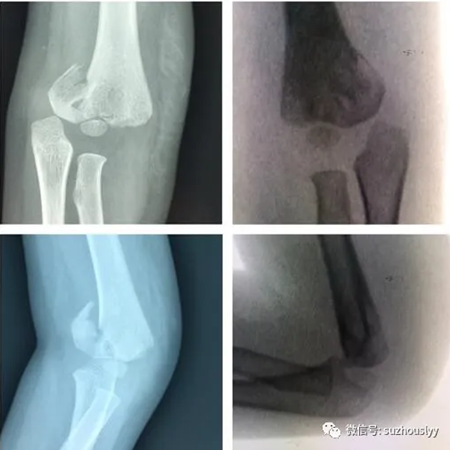

科主任刘长征高度关注,组织多学科协作会诊。在儿童重症医学科杨林风主任、心胸外科主任汪端、麻醉科主任梅厚连、普外科主治医师张翔等多学科共同评估病情、讨论手术风险及手术时机方案后,最终决定行手术治疗。由于伤后10天,术前讨论闭合微创手术难度较大,预行切开复位骨折内固定术。

一分钟手法闭合完全解剖复位(对比图)

手术当天,由儿童骨科主治医师年争好主刀,成功进行了皮肤不切口闭合复位、经皮穿钢针固定的微创手术。手术非常成功,达到了完美的完全解剖复位,经过骨一科医护的精心治疗,患儿顺利康复出院。